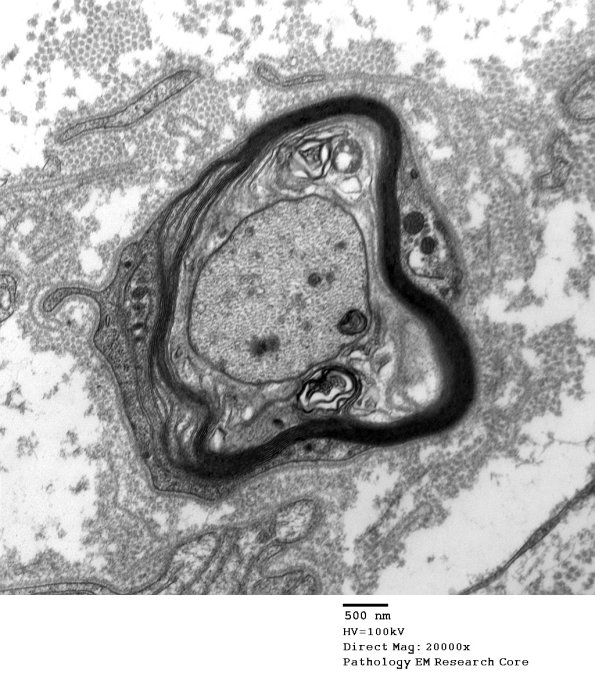

4C3 In this case the density of axonal organelles, especially cytoskeleton, and axolemmal thickening suggests this is a paranode adjacent to a node of Ranvier. (electron micrograph)